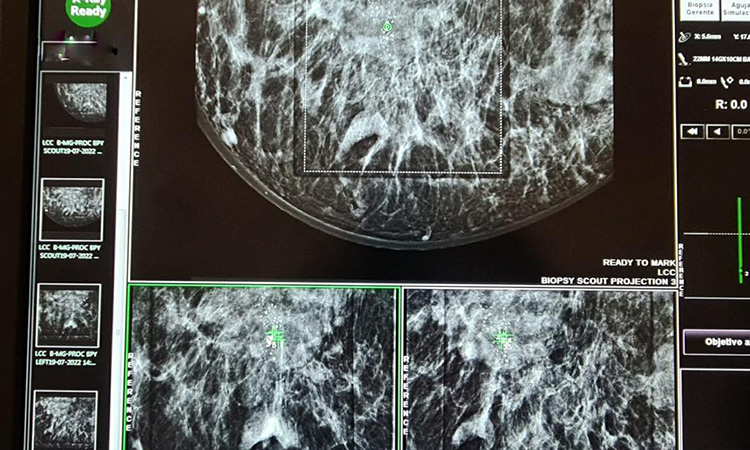

Miguel Bernardo Romero Flores, director de Hospital General de Mexicali (HGM), comentó que el estudio de biopsia por esterotaxia es sofisticado y se realiza en mujeres con alguna alteración en su mamografía, como lo pueden ser las microcalcificaciones; es un procedimiento de alta precisión que se hace a través del mastógrafo, el cual consta con una duración de 40 a 60 minutos.

Por su parte, Nitza Benitez Pérez, coordinadora de Equidad de Género y Salud Reproductiva de la Jurisdicción de Servicios de Salud Mexicali, informó que cuando una paciente con edad de 40 a 59 años tiene alguna alteración en su mastografía, y reporta micro calcificaciones que sean sospechosas para algún tipo de cáncer, se recomienda este estudio.

Una de las ventajas, es que, a diferencia del ultrasonido, amplifica la imagen y se pueden evaluar lesiones sospechosas. Además, es un procedimiento menos invasivo que la biopsia que se realiza a través de un procedimiento quirúrgico.